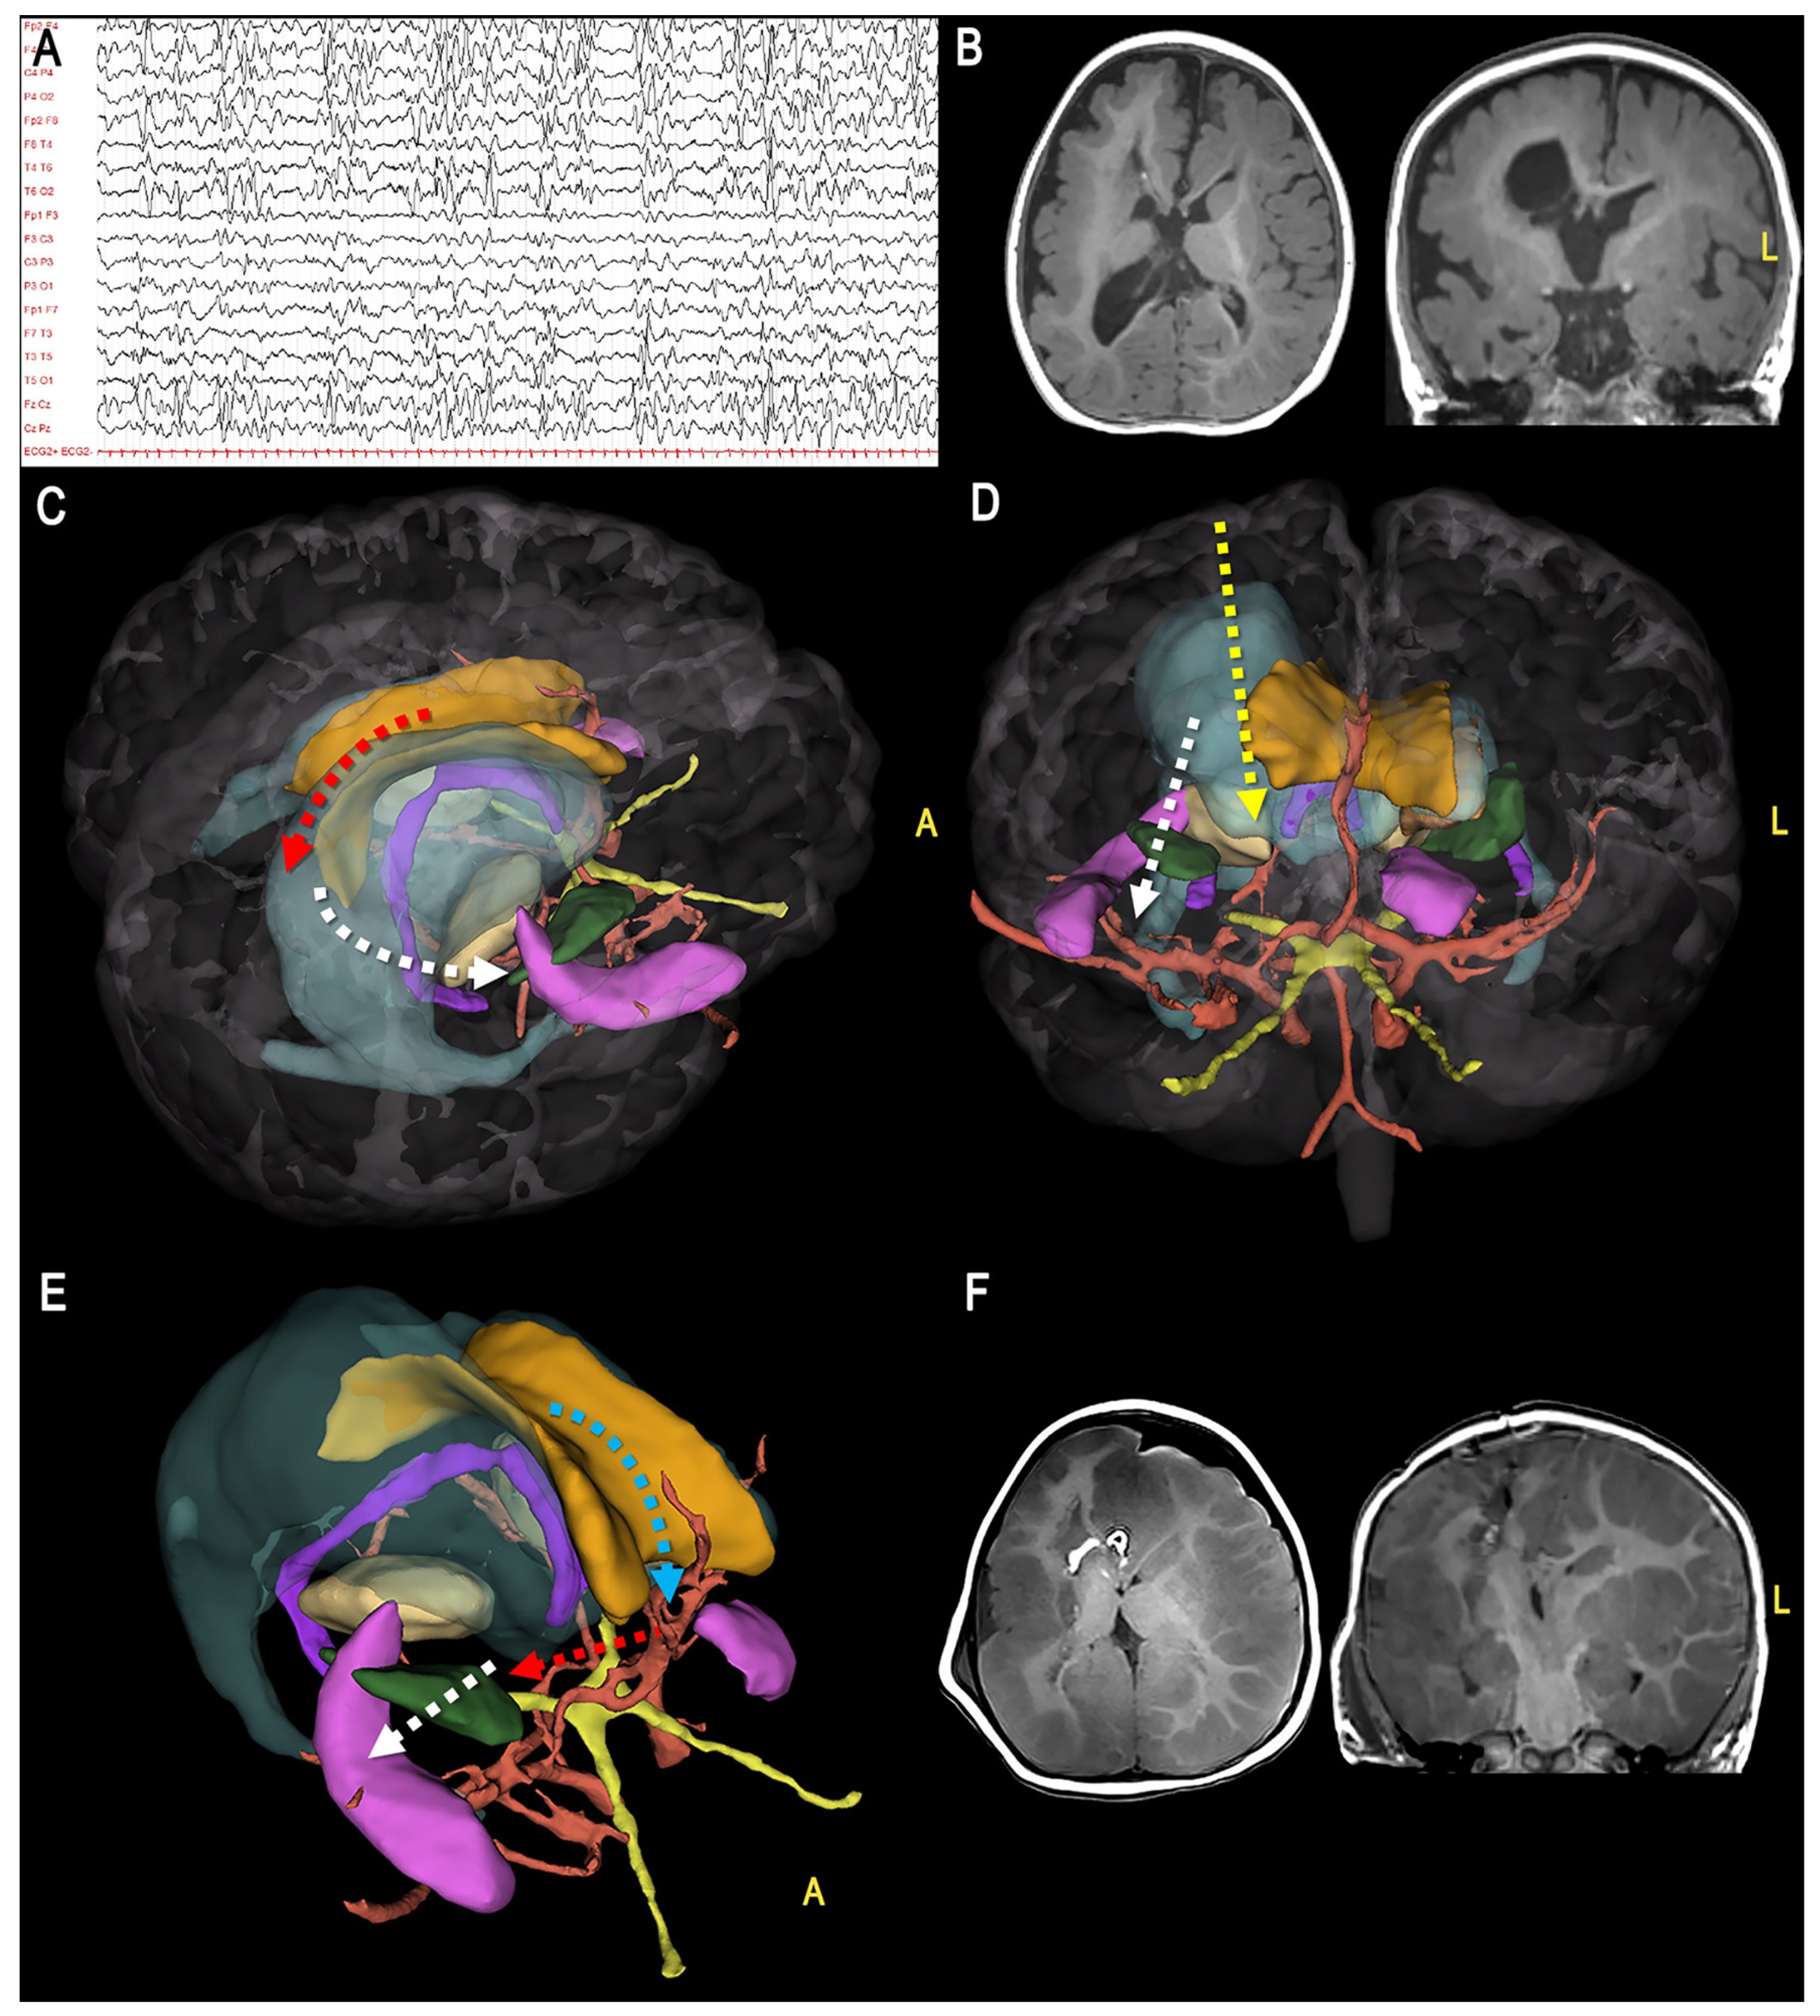

2.1. Illustrative Cases

3. Results

3.1. 3D Modeling

3.2. Augmented Reality